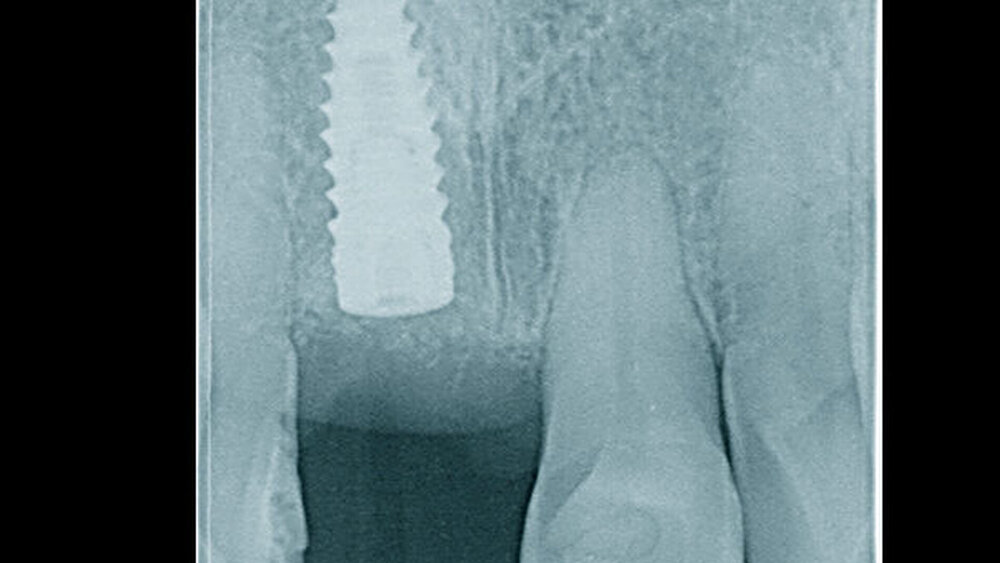

In welchen klinischen Anwendungen bietet das Implantat Vorteile?Hermann:Das neue CAMLOG PROGRESSIVE-LINE Implantat besticht durch sein innovatives parallel-konisches Makrodesign mit einem speziellen Gewinde, bei gleichzeitig bewährter Prothetikschnittstelle der Camlog-Linie. Dies bedeutet, dass in der chirurgischen Phase mit diesem Implantat eine zuverlässige Primärstabilität erzielt werden kann, speziell bei schwierigen anatomischen Voraussetzungen, wie z. B. bei der Sofortimplantation, bei reduzierter Kieferkammbreite oder konkav verlaufenden Alveoloarkämmen sowie bei weichem Knochen im Oberkiefer. Aufgrund des krestalen Verankerungsgewindes sehen wir zudem einen Vorteil bei der Platzierung des Implantats im Zusammenhang mit einer simultanen, offenen Sinusbodenelevation bei stark reduzierter Restknochenhöhe (2–3 mm). Auch einzeitige Verfahren lassen sich einfacher durchführen. Denn auch im kompromittierten Knochen erreicht das Implantat eine hohe vorhersagbare Primärstabilität.